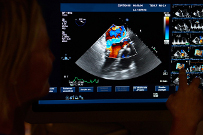

Клиника занимается хирургическим лечением всего спектра врождённых и приобретённых кардиологических заболеваний (включая искусственные импланты), в том числе у детей и новорожденных.

Здесь широко применяются минимально-инвазивные методы, преимуществами которых является не только меньшая травматичность в связи с небольшими разрезами, но и возможность для хирурга выполнять операцию на работающем сердце без необходимости в искусственном кровообращении.

Сочетание современных технологий и огромного опыта хирургов позволяет достичь самых надёжных результатов в лечении больных, страдающих сердечно-сосудистыми заболеваниями.